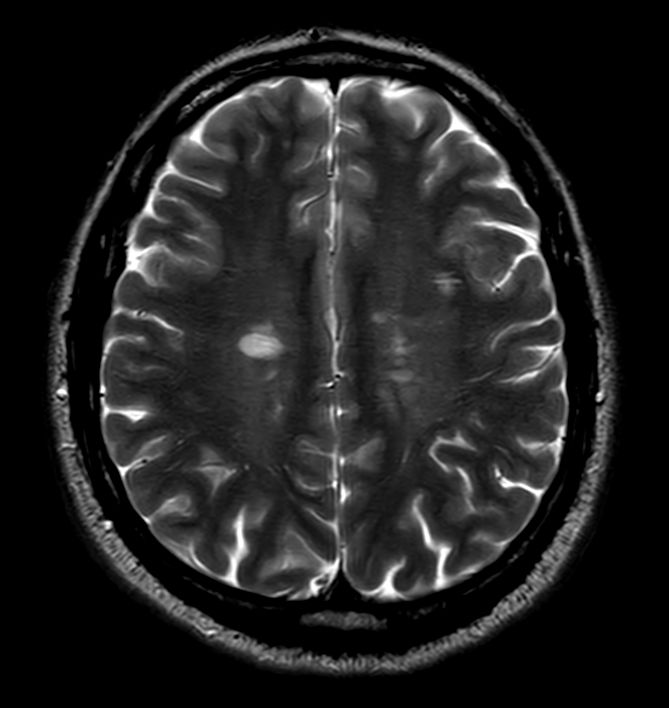

Axial T2w FFE